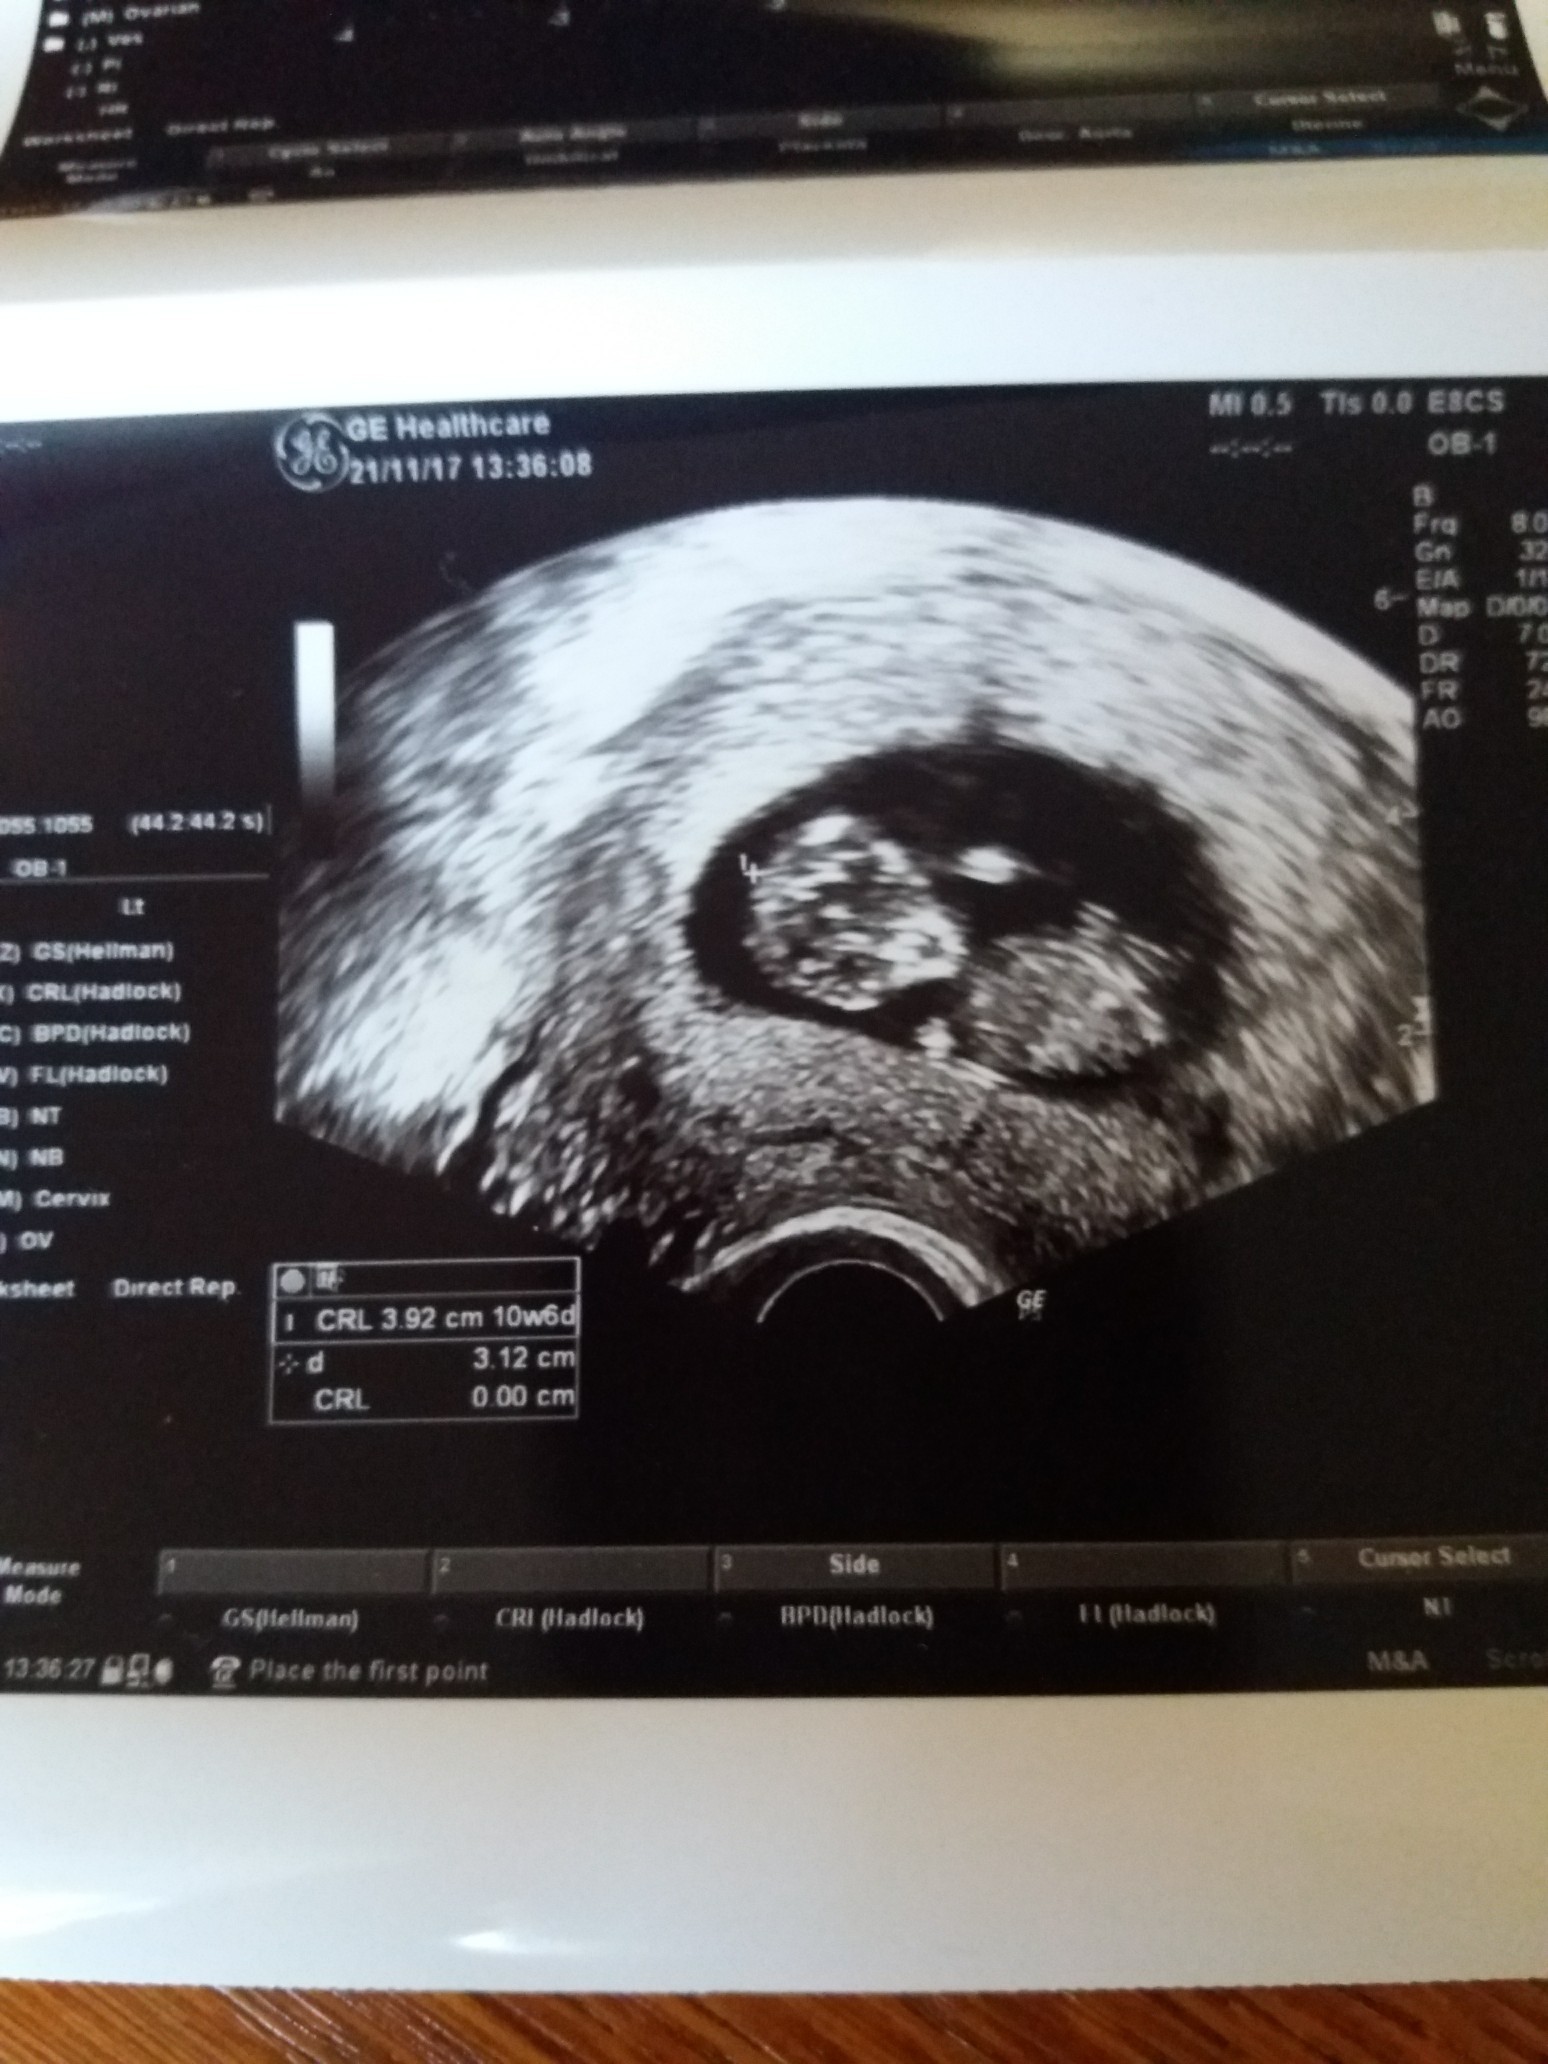

Wrzucam zdjecie 10t6d

Zobacz załącznik 829888